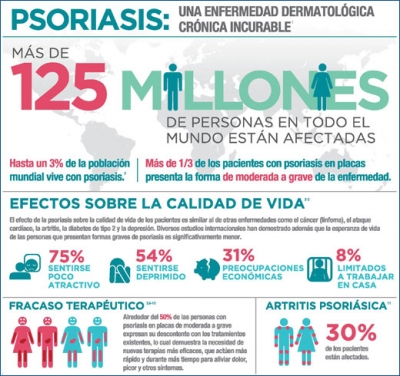

OMS: Reporte Global de Psoriasis

Según lo publicado en el último reporte global de la Organización Mundial de la Salud sobre psoriasis, esta enfermedad tiene una prevalencia a nivel mundial que oscila entre el 2 y el 3% de la población, afectando a casi 125 millones de personas en todo el planeta de cualquier edad.